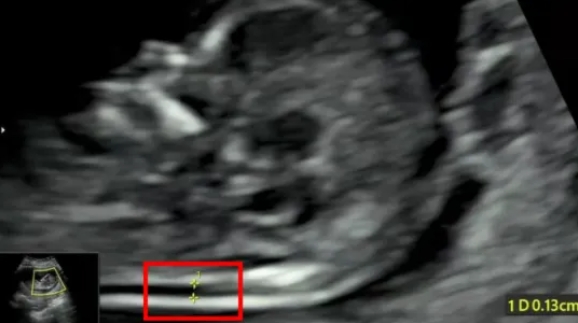

在为孕妈妈们做NT检查的同时,对于胎儿的结构也进行了详细的检查,并且发现了多例胎儿严重结构缺陷。

检查选在孕11~13周+6天进行,相当于头臀长45-84mm时测量,超过84mm检查结果会不准确。

NT增厚越明显,胎儿异常机会就越高,异常程度也会越严重。一般正常的NT厚度不能大于3mm,超过3mm表示NT增厚,存在异常可能。